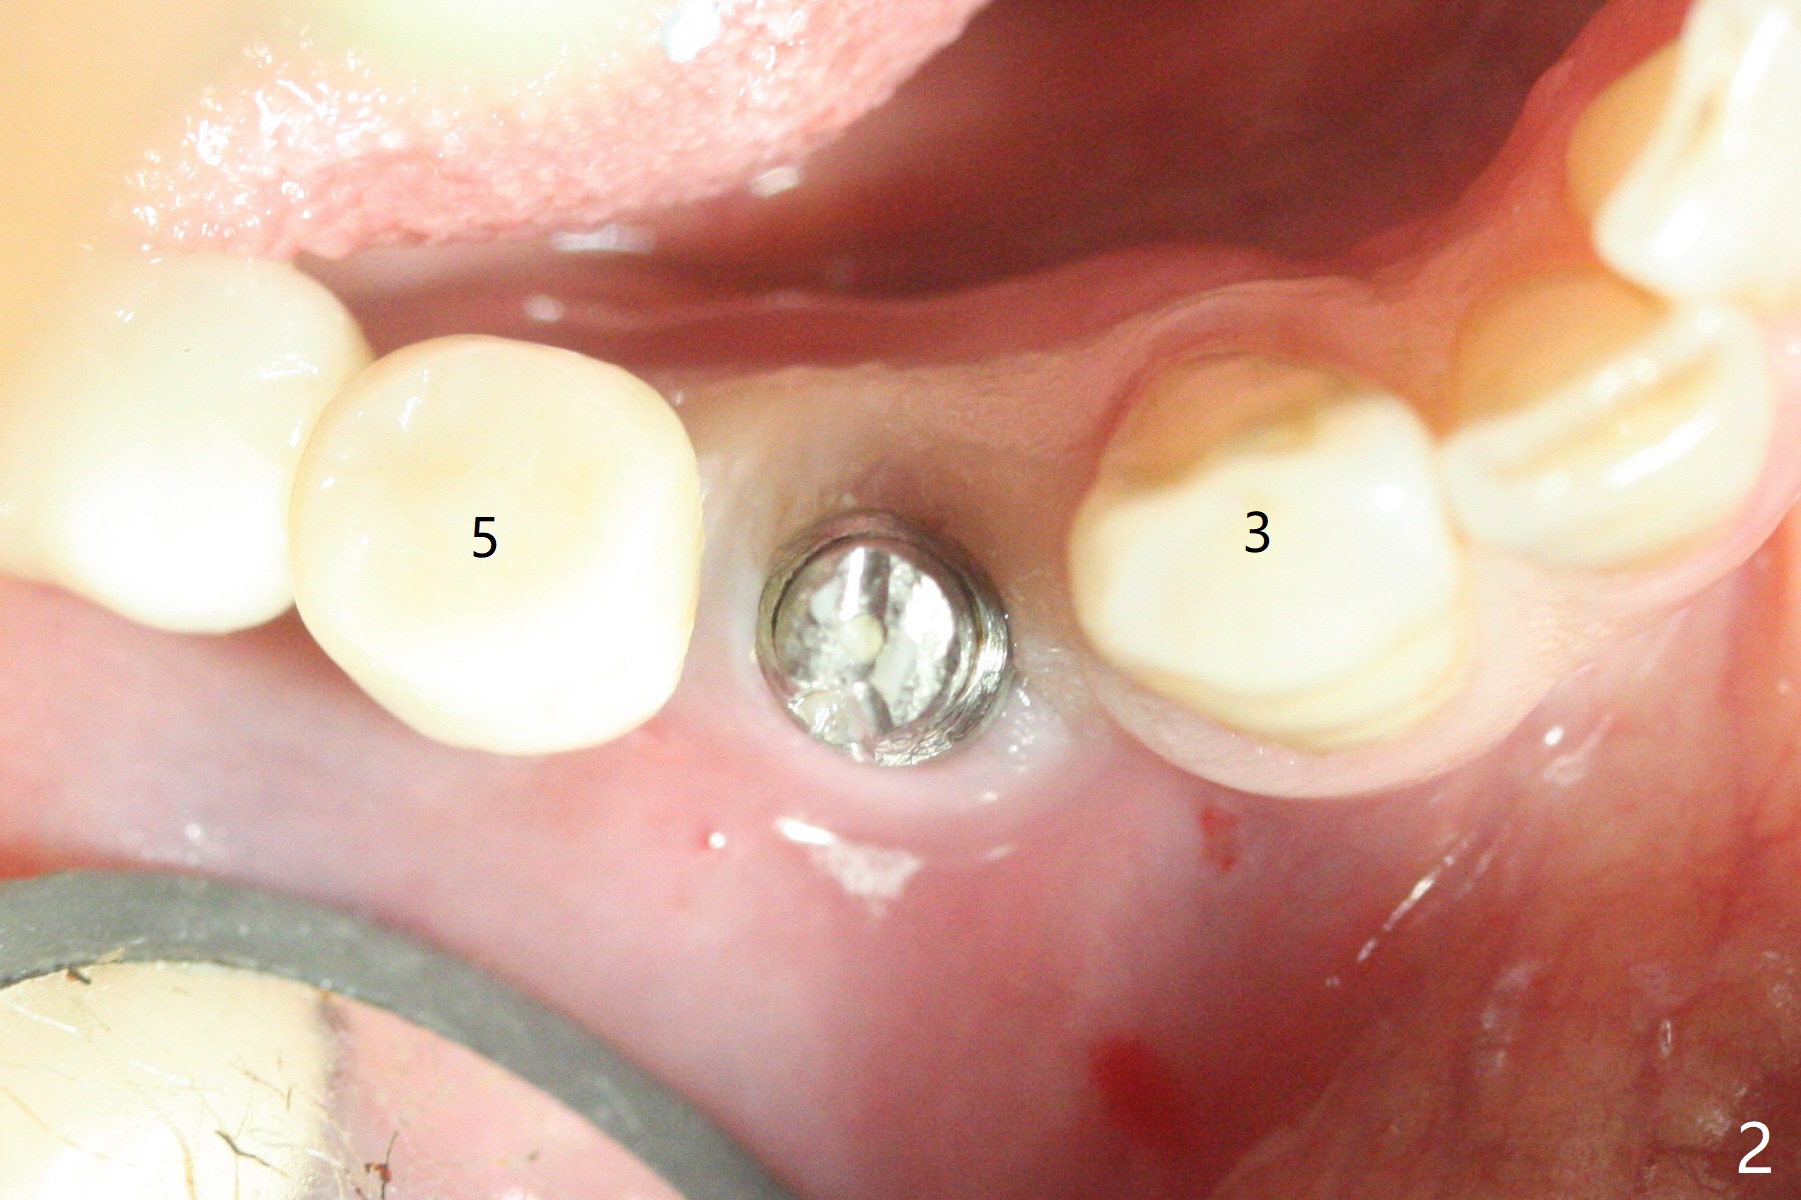

61岁女右下4(粘固后5.5年)植体周围炎(颊侧牙龈没有角化龈(图一:*)),因为颊侧种植(图二),翻瓣证实(图三),取出4.5毫米两段式植体,在舌侧骨质(图四:L)即刻植入2.5毫米一段式植体(图五),颊侧缺损植入大量粘性骨粉(图六:*),覆盖PRF膜后,缝合(图七),与图二对比,窄植体明显舌侧移位。术后一个月撤除牙周敷料(图八),并没有马上制作临时牙冠,让病人容易搞好局部卫生,促进伤口愈合(图九),术后三个月塞入龈线(图十:^),制备基台,植体在牙槽嵴中性位置(颊舌侧),但愿颊侧有足够再生骨质,覆盖植体螺纹。